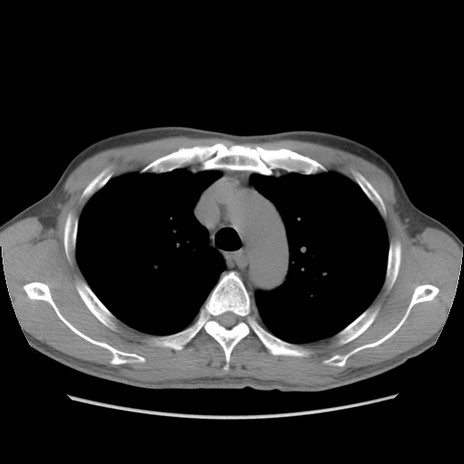

症例56 CT(横断像)

脂肪ウインドウ